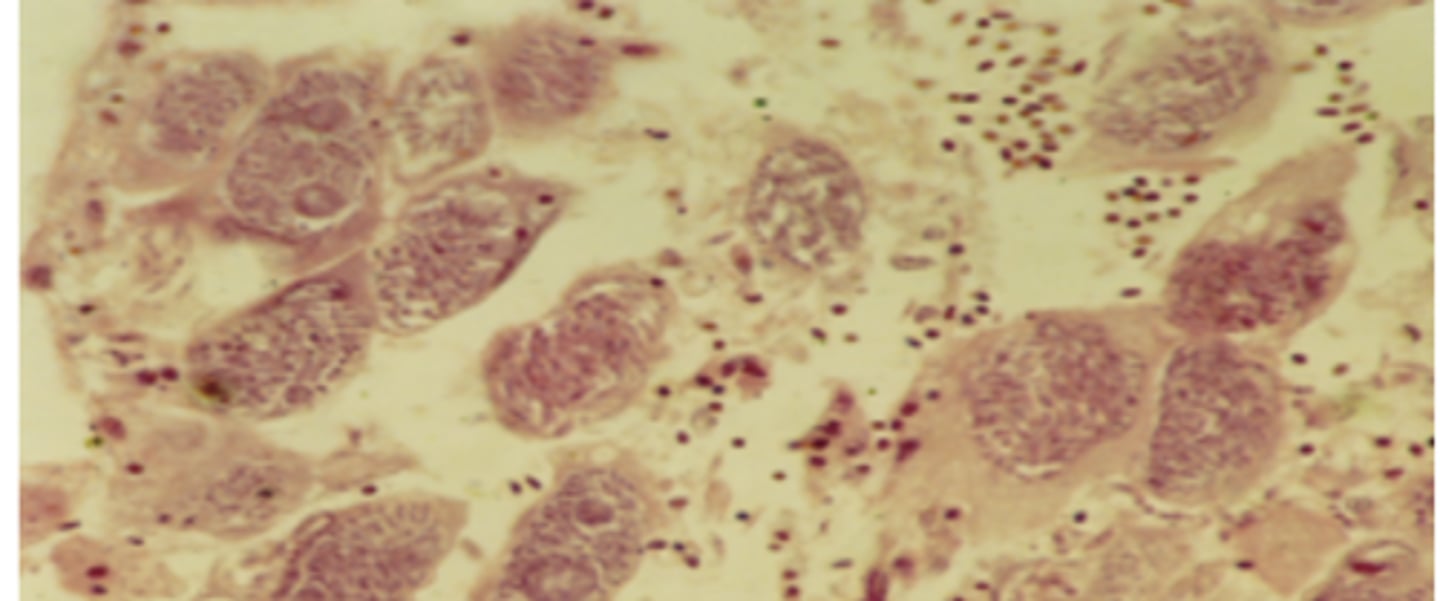

Slide from a dead chicken - What parasite and life stage is this?

Eimeria spp. - Merozoites (banana-shaped, central red nuclei)

Eimeria spp. - Microgametocyte (see many small microgamonts within cell)

Eimeria spp. - Schizonts (many merozoites within them)

Eimeria spp. - Macrogametocyte (see wall forming bodies)